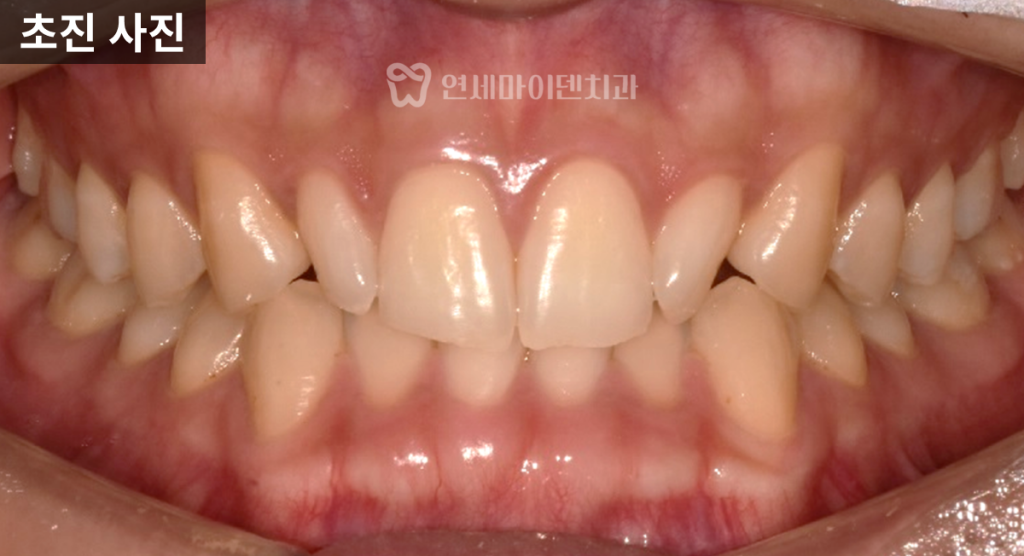

20대 교정 진단과 초기 상태

이번 환자는 20대 중반으로,

앞니가 고르지 않고 돌아가 있었으며

아래 앞니는 안쪽으로 많이 쓰러진 상태였습니다.

단순한 치아 배열 문제로 보일 수 있었지만,

정밀 진단 결과

위턱 전체의 폭이 좁고

치아들이 안쪽으로 몰려 있는 구조였습니다.

특히 두 번째 앞니는

크기가 작은 왜소치 형태를 띠고 있었고,

사랑니는 매복된 상태로

발치가 필요한 상황이었습니다.

다행히 전반적인 치근 상태는

양호한 편이었습니다.

얼굴 사진에서도

치아가 안쪽으로 쓰러지며

이른바 ‘입동굴’이 넓어 보였고,